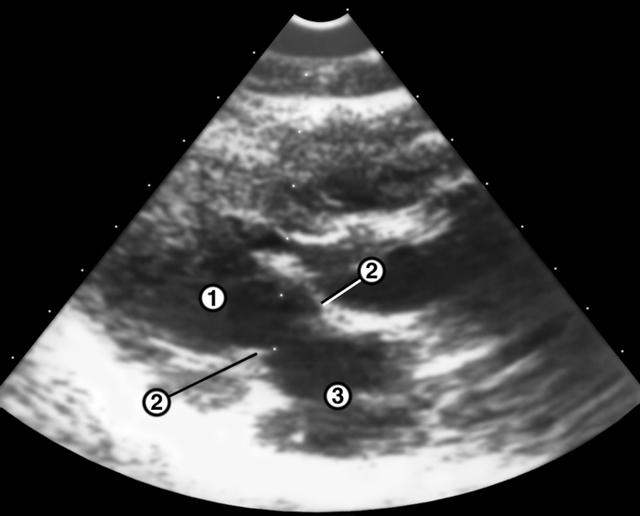

Рис. 2б). Эхокардиограмма при рестриктивной кардиомиопатии — незначительное расширение полости левого желудочка, не соответствующее степени утолщения и деформации створок митрального клапана. 1 — полость левого желудочка; 2 — митральный клапан; 3 — левое предсердие. |